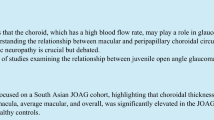

Following data acquisition, a 26 × 26 cube-grid centered in the optic disc was generated to automatically measure choroidal thickness. This grid included 676 cubes of 200 µm around the ONH, including the 88 central cubes corresponding to the ONH area that were not analyzed; thus the DRI-OCT Triton displays choroidal thickness for a total of 588 peripapillary cubes (Fig. 1a). The Bruch membrane and choroidal–scleral interface were delineated with the segmentation algorithm implemented by Topcon.

Peripapillary choroid grid. a Image of the 26 × 26 cube-grid centered in the optic disc of a right eye obtained with deep range imaging (DRI) optical coherence tomography (OCT) Triton (Topcon Corporation, Tokyo, Japan). This grid includes 676 cubes of 200 µm around the optic disc: the 88 central cubes corresponding to the optic disc area are not measured, and the DRI-OCT Triton automatically displays choroidal thickness in each of the 588 peripapillary cubes. b Schematic representation of the peripapillary choroidal thickness zones defined in this study (superior temporal, superior central, superior nasal, inferior temporal, inferior central, and inferior nasal) bounded by a red line

For the statistical analysis, the PPCT OCT grid was divided into the following seven zones: superior temporal, superior central, superior nasal, inferior temporal, inferior central, inferior nasal, and the ONH (Fig. 1b). Study zones were set according to their position around the ONH; the central superior zone included 86 cubes directly positioned above the ONH, and the central inferior zone included the 86 points below the ONH. The four squares beyond the ONH were labeled as temporal superior, temporal inferior (104 cubes each), nasal superior, and nasal inferior (104 cubes each).